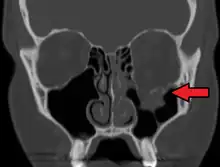

FractLeftOrbitFloorMark

orbital blowout fracture demonstrating enophthalmos

Thin cut (2-3mm) CT scan with axial and coronal view is the optimal study of choice for orbital fractures.[16][17]